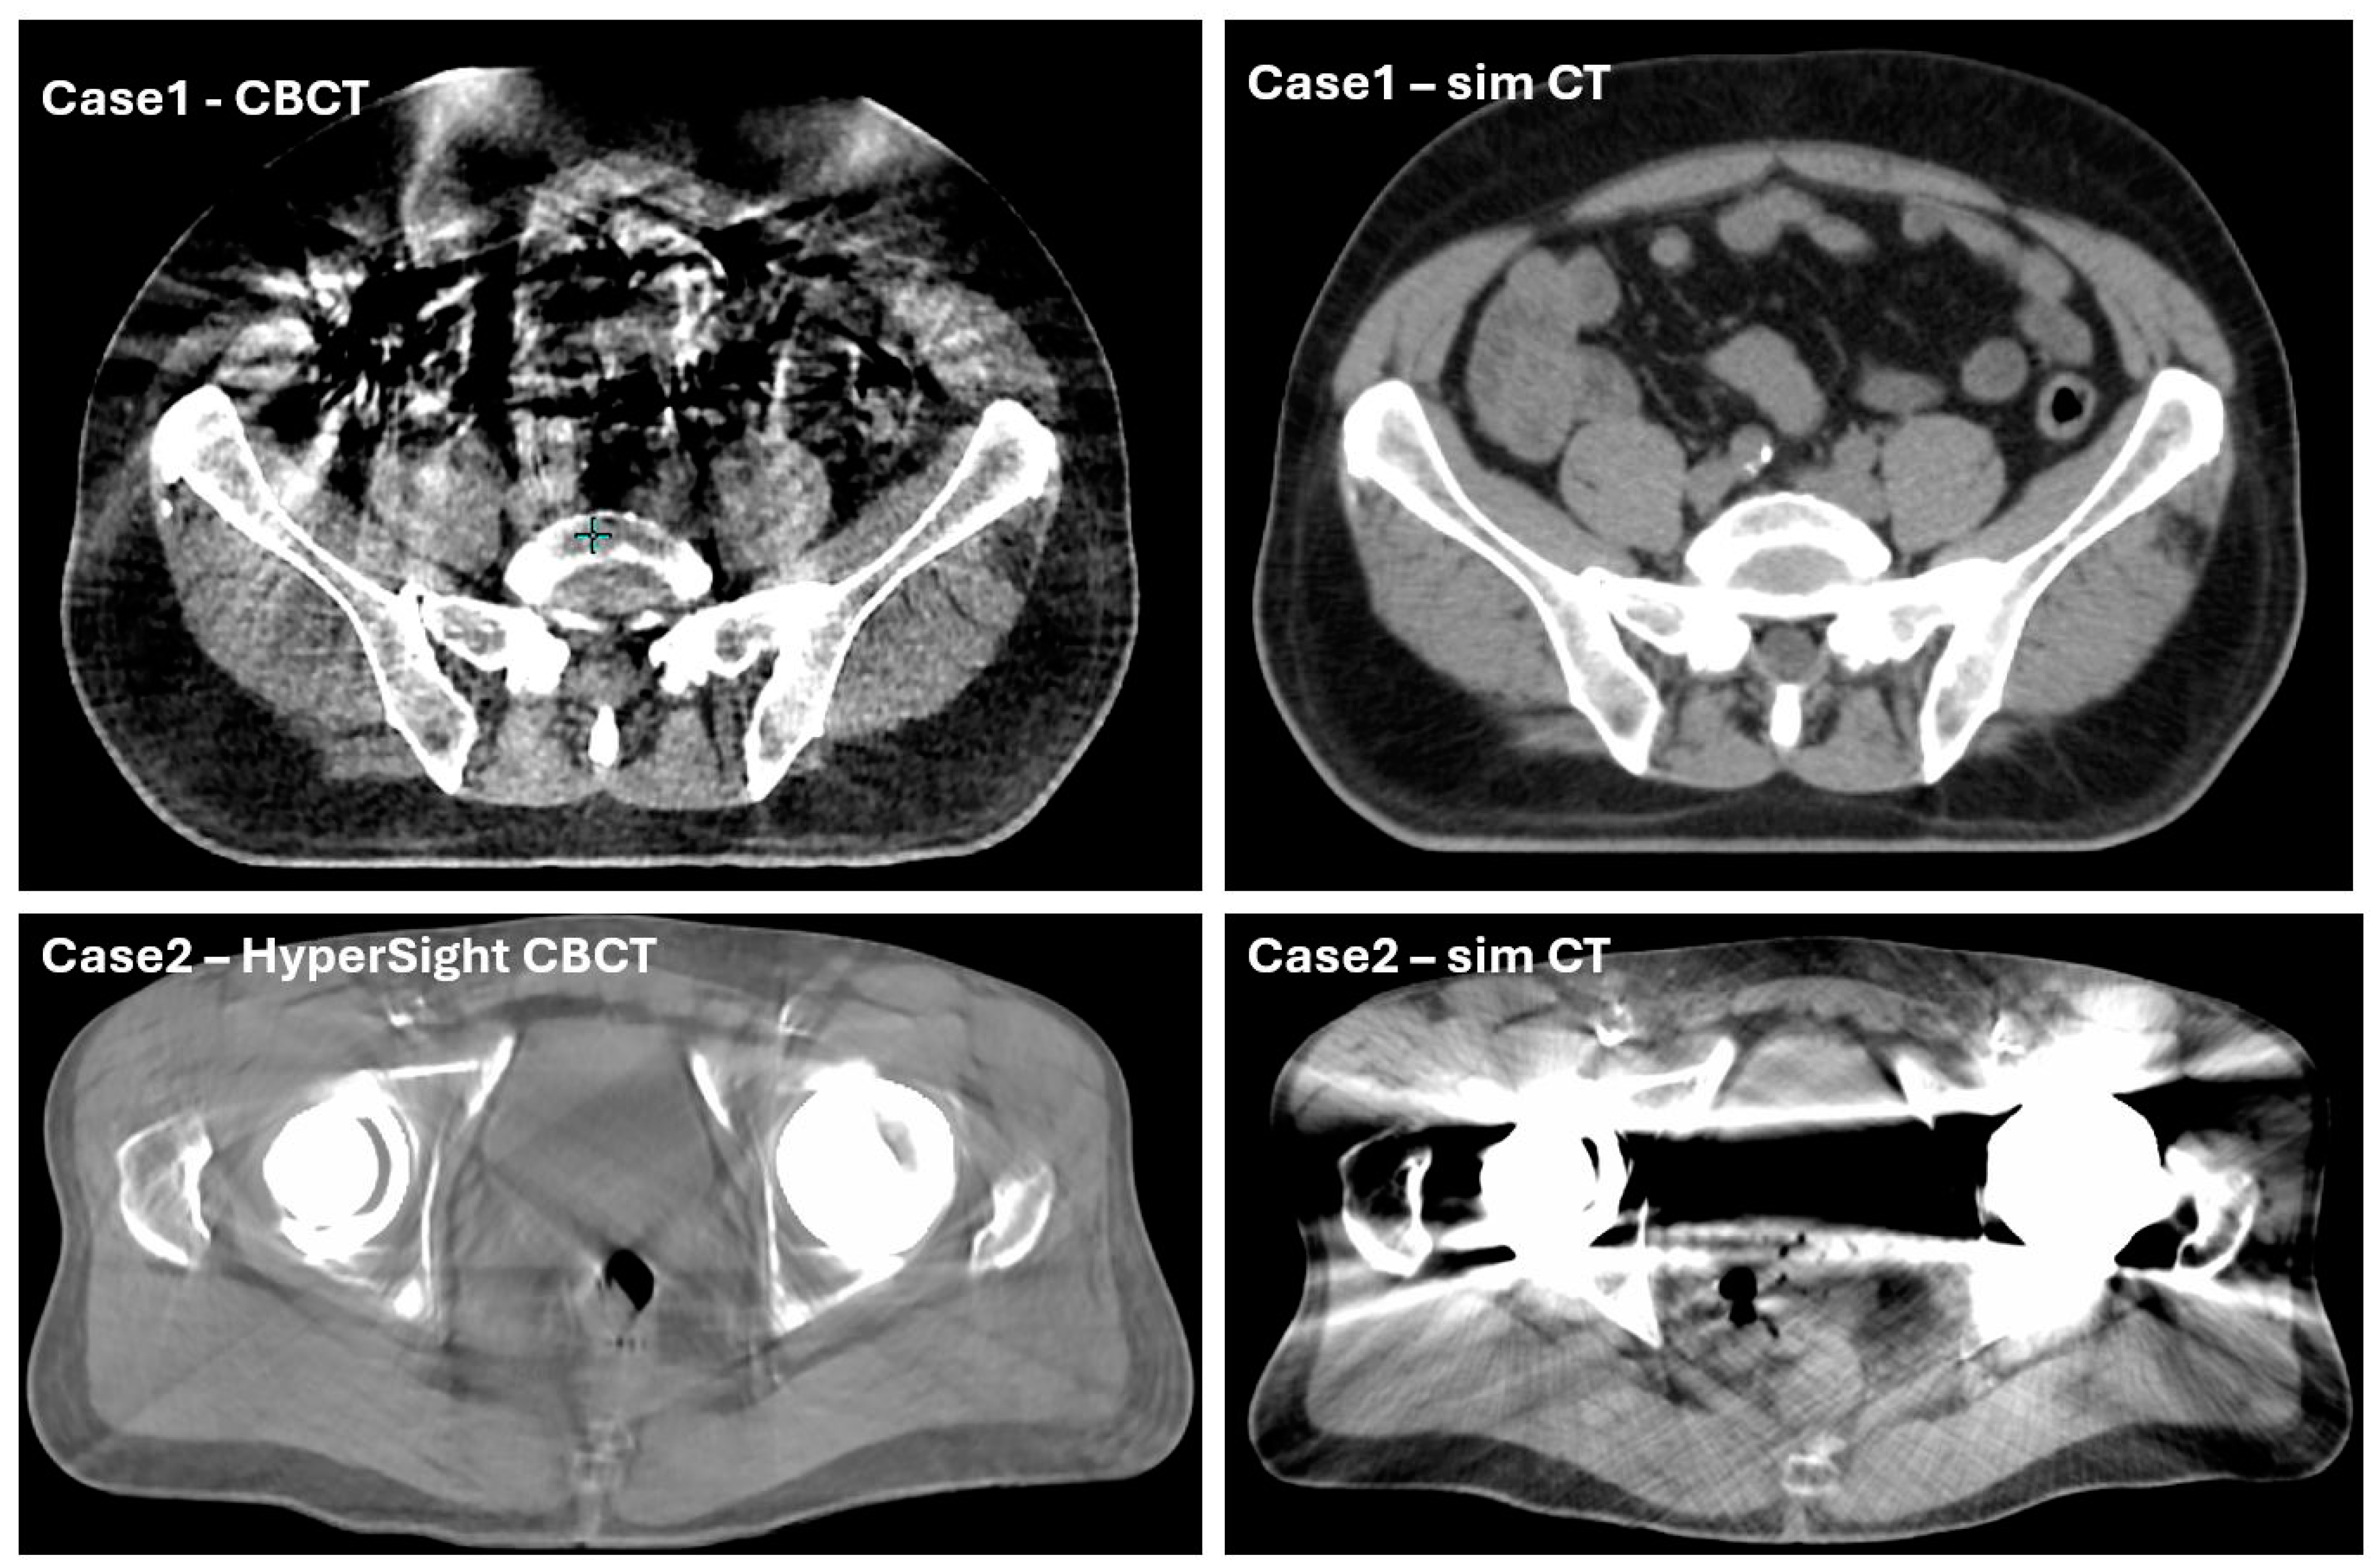

3.2.1. System-Driven Issues

| Reduced auto-contouring accuracy due to imaging artifacts | 20% estimated with varying severity, not quantified | <5% estimated, not quantified | |

| Inaccurate air mapping from CBCT to sCT | 20% estimated with varying severity, not quantified | 10% estimated, not quantified | |